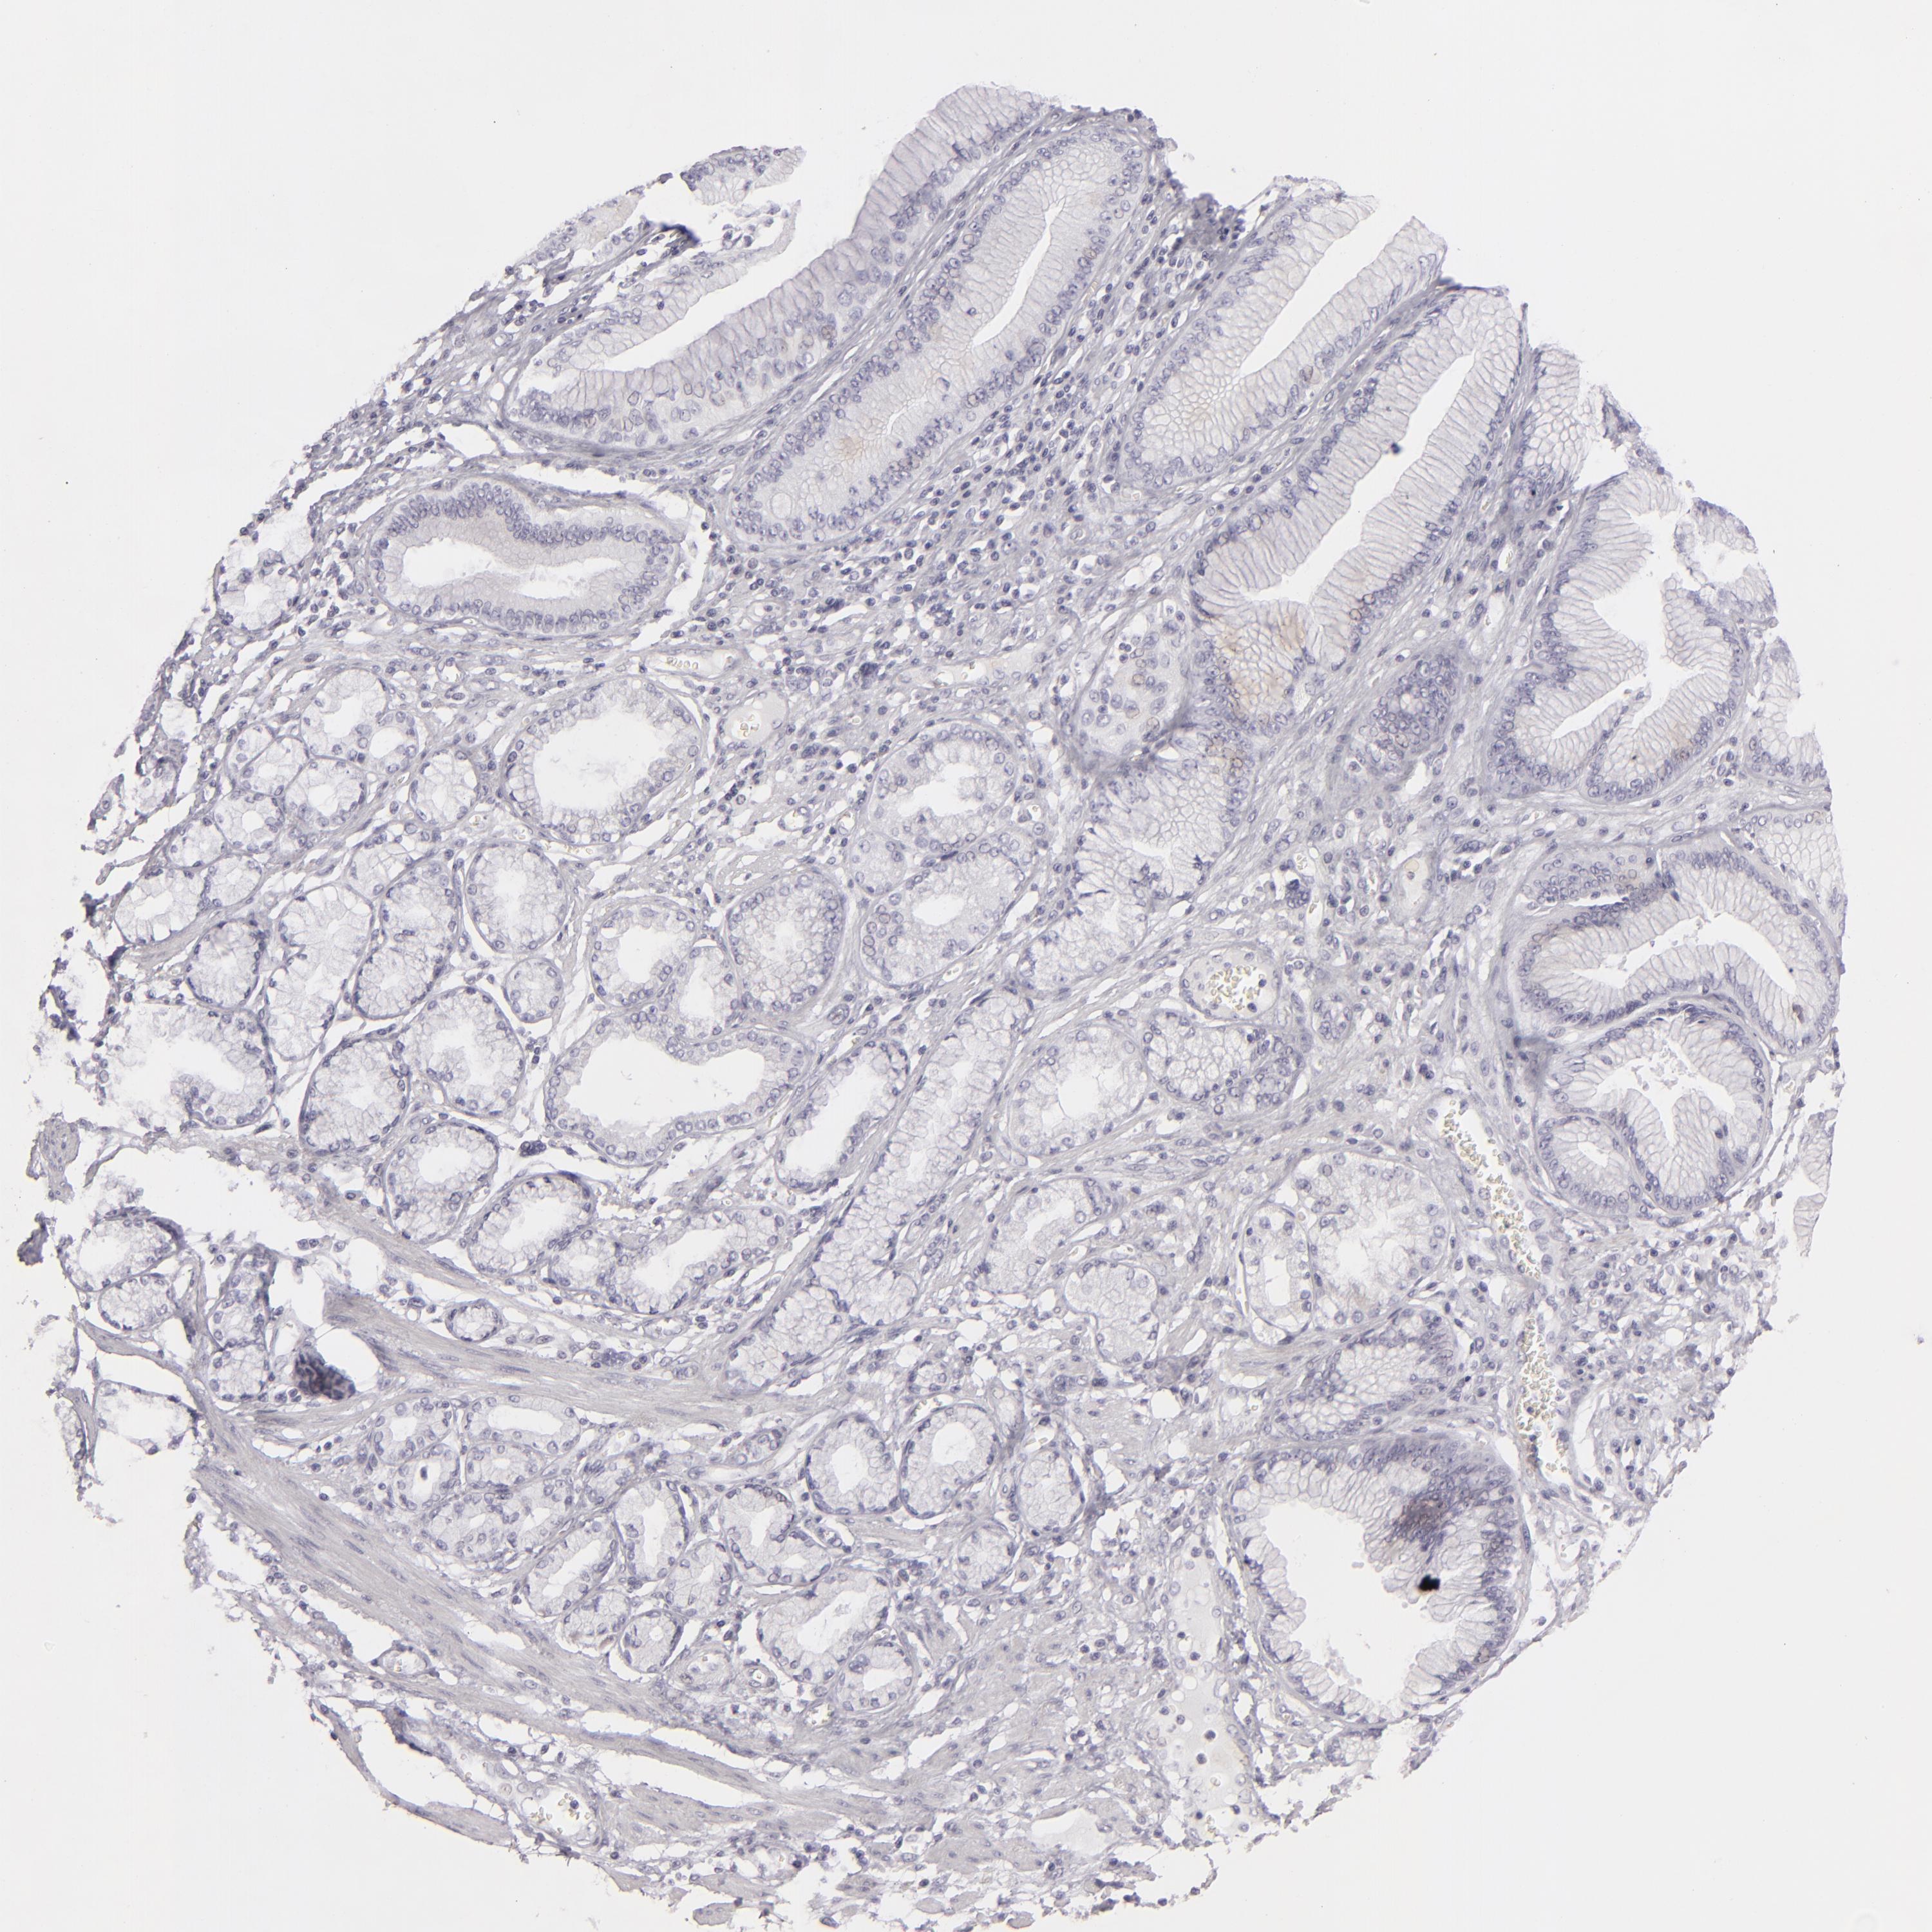

STOMACH CANCER - Protein expressioni

A mouse-over function shows sample information and annotation data. Click on an image to view it in a full screen mode. Samples can be filtered based on level of antibody staining by selecting one or several of the following categories: high, medium, low and not detected. The assay and annotation is described here.

Note that samples used for immunohistochemistry by the Human Protein Atlas do not correspond to samples in the TCGA dataset.

Antibody stainingi

Antibody staining in the annotated cell types in the current human tissue is reported as not detected, low, medium, or high, based on conventional immunohistochemistry profiling in selected tissues. This score is based on the combination of the staining intensity and fraction of stained cells.

Each image is clickable and will lead to virtual microscopy that enables deeper exploration of all samples and also displays staining intensity scores, fraction scores and subcellular localization as well as patient and tissue information for each sample.

Antibody CAB002221

Staining

High

Medium

Low

Not detected

Intensity

Strong

Moderate

Weak

Negative

Quantity

>75%

75%-25%

<25%

None

Location

Nuclear

Cytoplasmic/membranous

Cytoplasmic/membranous,nuclear

Adenocarcinoma, NOS